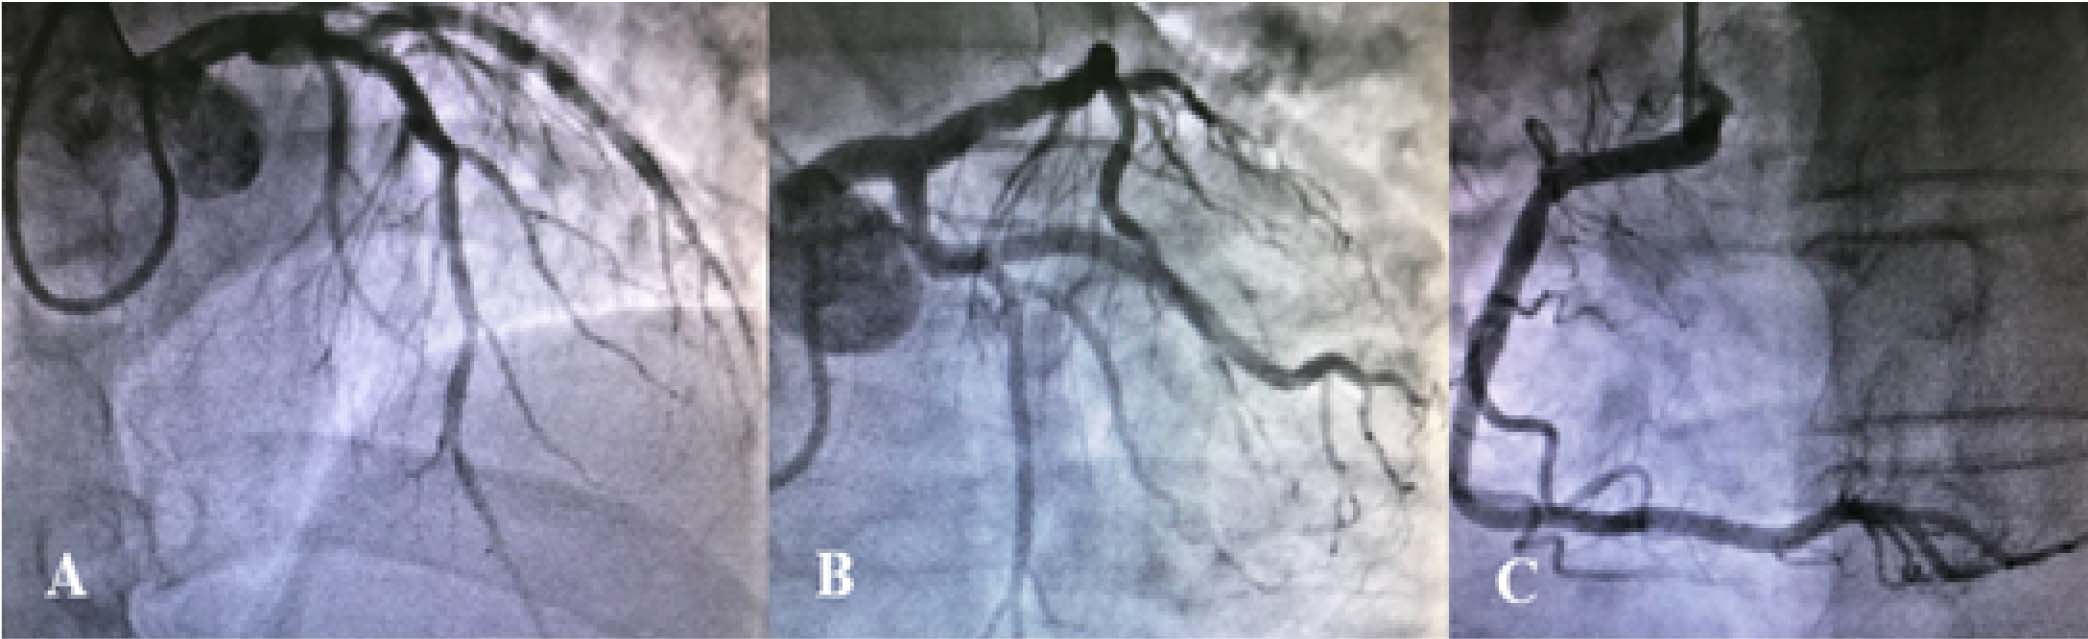

Se realizó coronariografía a las dos horas del inicio del cuadro clínico del paciente, donde no se observa obstrucción, estenosis significativa ni evidencia de ruptura aguda de placa en ninguna arteria epicárdica, incidentalmente se evidencia estenosis del 60% en origen de una rama diagonal de tamaño mediano con flujo distal conservado ( Figura 2); en el ventriculograma se evidenció discinesia apical e hipercinesia basal ( Figura 3).

En el caso presentado, se esperaba encontrar obstrucción de la arteria coronaria derecha ó menos probable, la arteria circunfleja, sin embargo las mismas se encontraban sin lesiones angiográficas, por lo que se efectuó ventriculografía donde se observó discinesia apical e hipercinesia basal 3, 4. Fue de esta manera que con el antecedente de estrés emocional y las alteraciones electrocardiográficas se planteó el diagnóstico de Miocardiopatía por estrés o Síndrome de Takotsubo cumpliendo los criterios de la Clínica Mayo 5- 9.